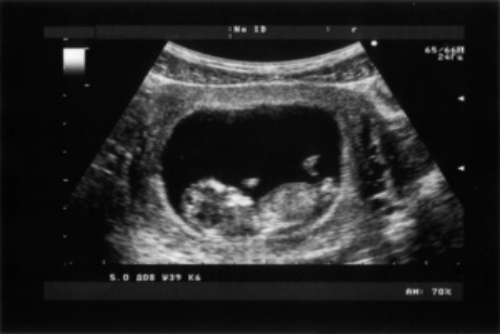

產(chǎn)前超聲檢查,是指醫(yī)生通過超聲波檢查孕婦子宮內(nèi)胎兒的情況。通常情況下,產(chǎn)前超聲檢查可通過腹部或陰道呈現(xiàn)圖像,對(duì)子宮內(nèi)胎兒的情況進(jìn)行大體判斷,還可明確胎兒大小、胎位、羊水分布、胎盤等情況。

超聲檢測(cè)1

4、胎兒大小:通過超聲檢查測(cè)量胎兒的雙頂徑、腹圍以及股骨長度,了解胎兒的生長發(fā)育情況;

6、其他:通過超聲檢查可觀察到胎兒的大小與孕周是否符合,并觀察胎兒各個(gè)臟器發(fā)育情況,包括顱腦、胸腔、腹腔以及心臟等。